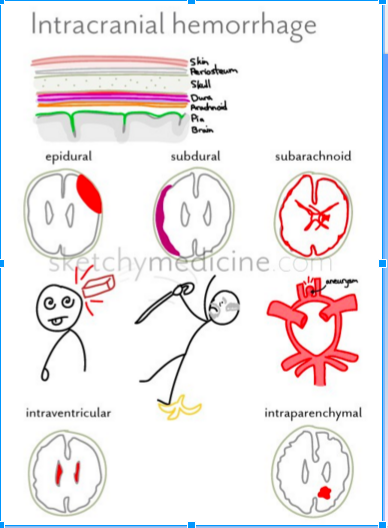

- What is a subarachnoid hemorrhage?

- Where is it at?

- What is a subdural hematoma and where is it at?

- What is an epidural hematoma and where is it at?

- WHat is a epidural hematoma associated with?

Subarachnoid hemorrhage (see picture-layered out on the surface of the brain)

- Arterial bleeding on the surface of the brain

- Between the pia mater and the arachnoid mater

Subdural hematoma

- Venous bleeding between the arachnoid and the dura mater

Epidural hematoma

- Dural artery or venous sinus bleeding between the skull and dura

- Associated with skull fracture

Describe the differences:

Epidural vs Subdural

2

See picture

Describe the following for Epidural, Subdural and Subarachnoid:

- In relation to the dura

- Respects suture lines?

- Trauma?

- What kind of blood and usually from where?

- Shape on CT?

- Clinical presentation?

Epidural

- Above the dura

- Respects suture lines

- High force trauma

- Arterial blood (commonly the middle meningeal artery)

- Lentiform (lens-shaped) or biconcave on CT

- Acute presentation

Subdural

- Below the dura

- Doesn’t respect suture lines

- Low force trauma

- Venous (from venous plexus)

- Cresent (banana-shaped) on CT

- May be insidious (worsening headache over days)

Subarachnoid

- Below the arachnoid

- No respect for anything

- Aneurysm rupture or high force trauma

- Arterial from the circle of Willis

- Lining surface, going into fissures and sulci and sella (death-star)

- Acute presentation (thunderclap headache)